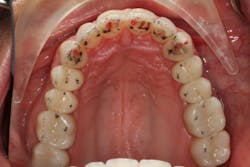

Darren remained in the provisionals for three months to allow the soft tissue to fully heal. This also allowed us to evaluate the esthetics, phonetics, occlusion, and function. The importance of provisional restorations cannot be understated, as they provide us with a trial before we place the definitive restorations.

The provisionals were especially important in this case as we had to work out the anterior guidance to be in harmony with the patient's envelope of function. When the provisional restorations were initially placed, Darren continued to feel “locked in” with the position and contours of his canines. Over several appointments, we had to slightly adjust his guidance until he was comfortable while still retaining the function and esthetics.

Finalizing a case, conservatively

Once we had confirmed the esthetics, phonetics, and function, we were ready to move forward with the definitive restorations. Photographs and impressions of the approved provisional restorations were given to the laboratory so the esthetics and occlusion that we worked out in the provisional phase could be duplicated and the information transferred to Darren’s final restorations.